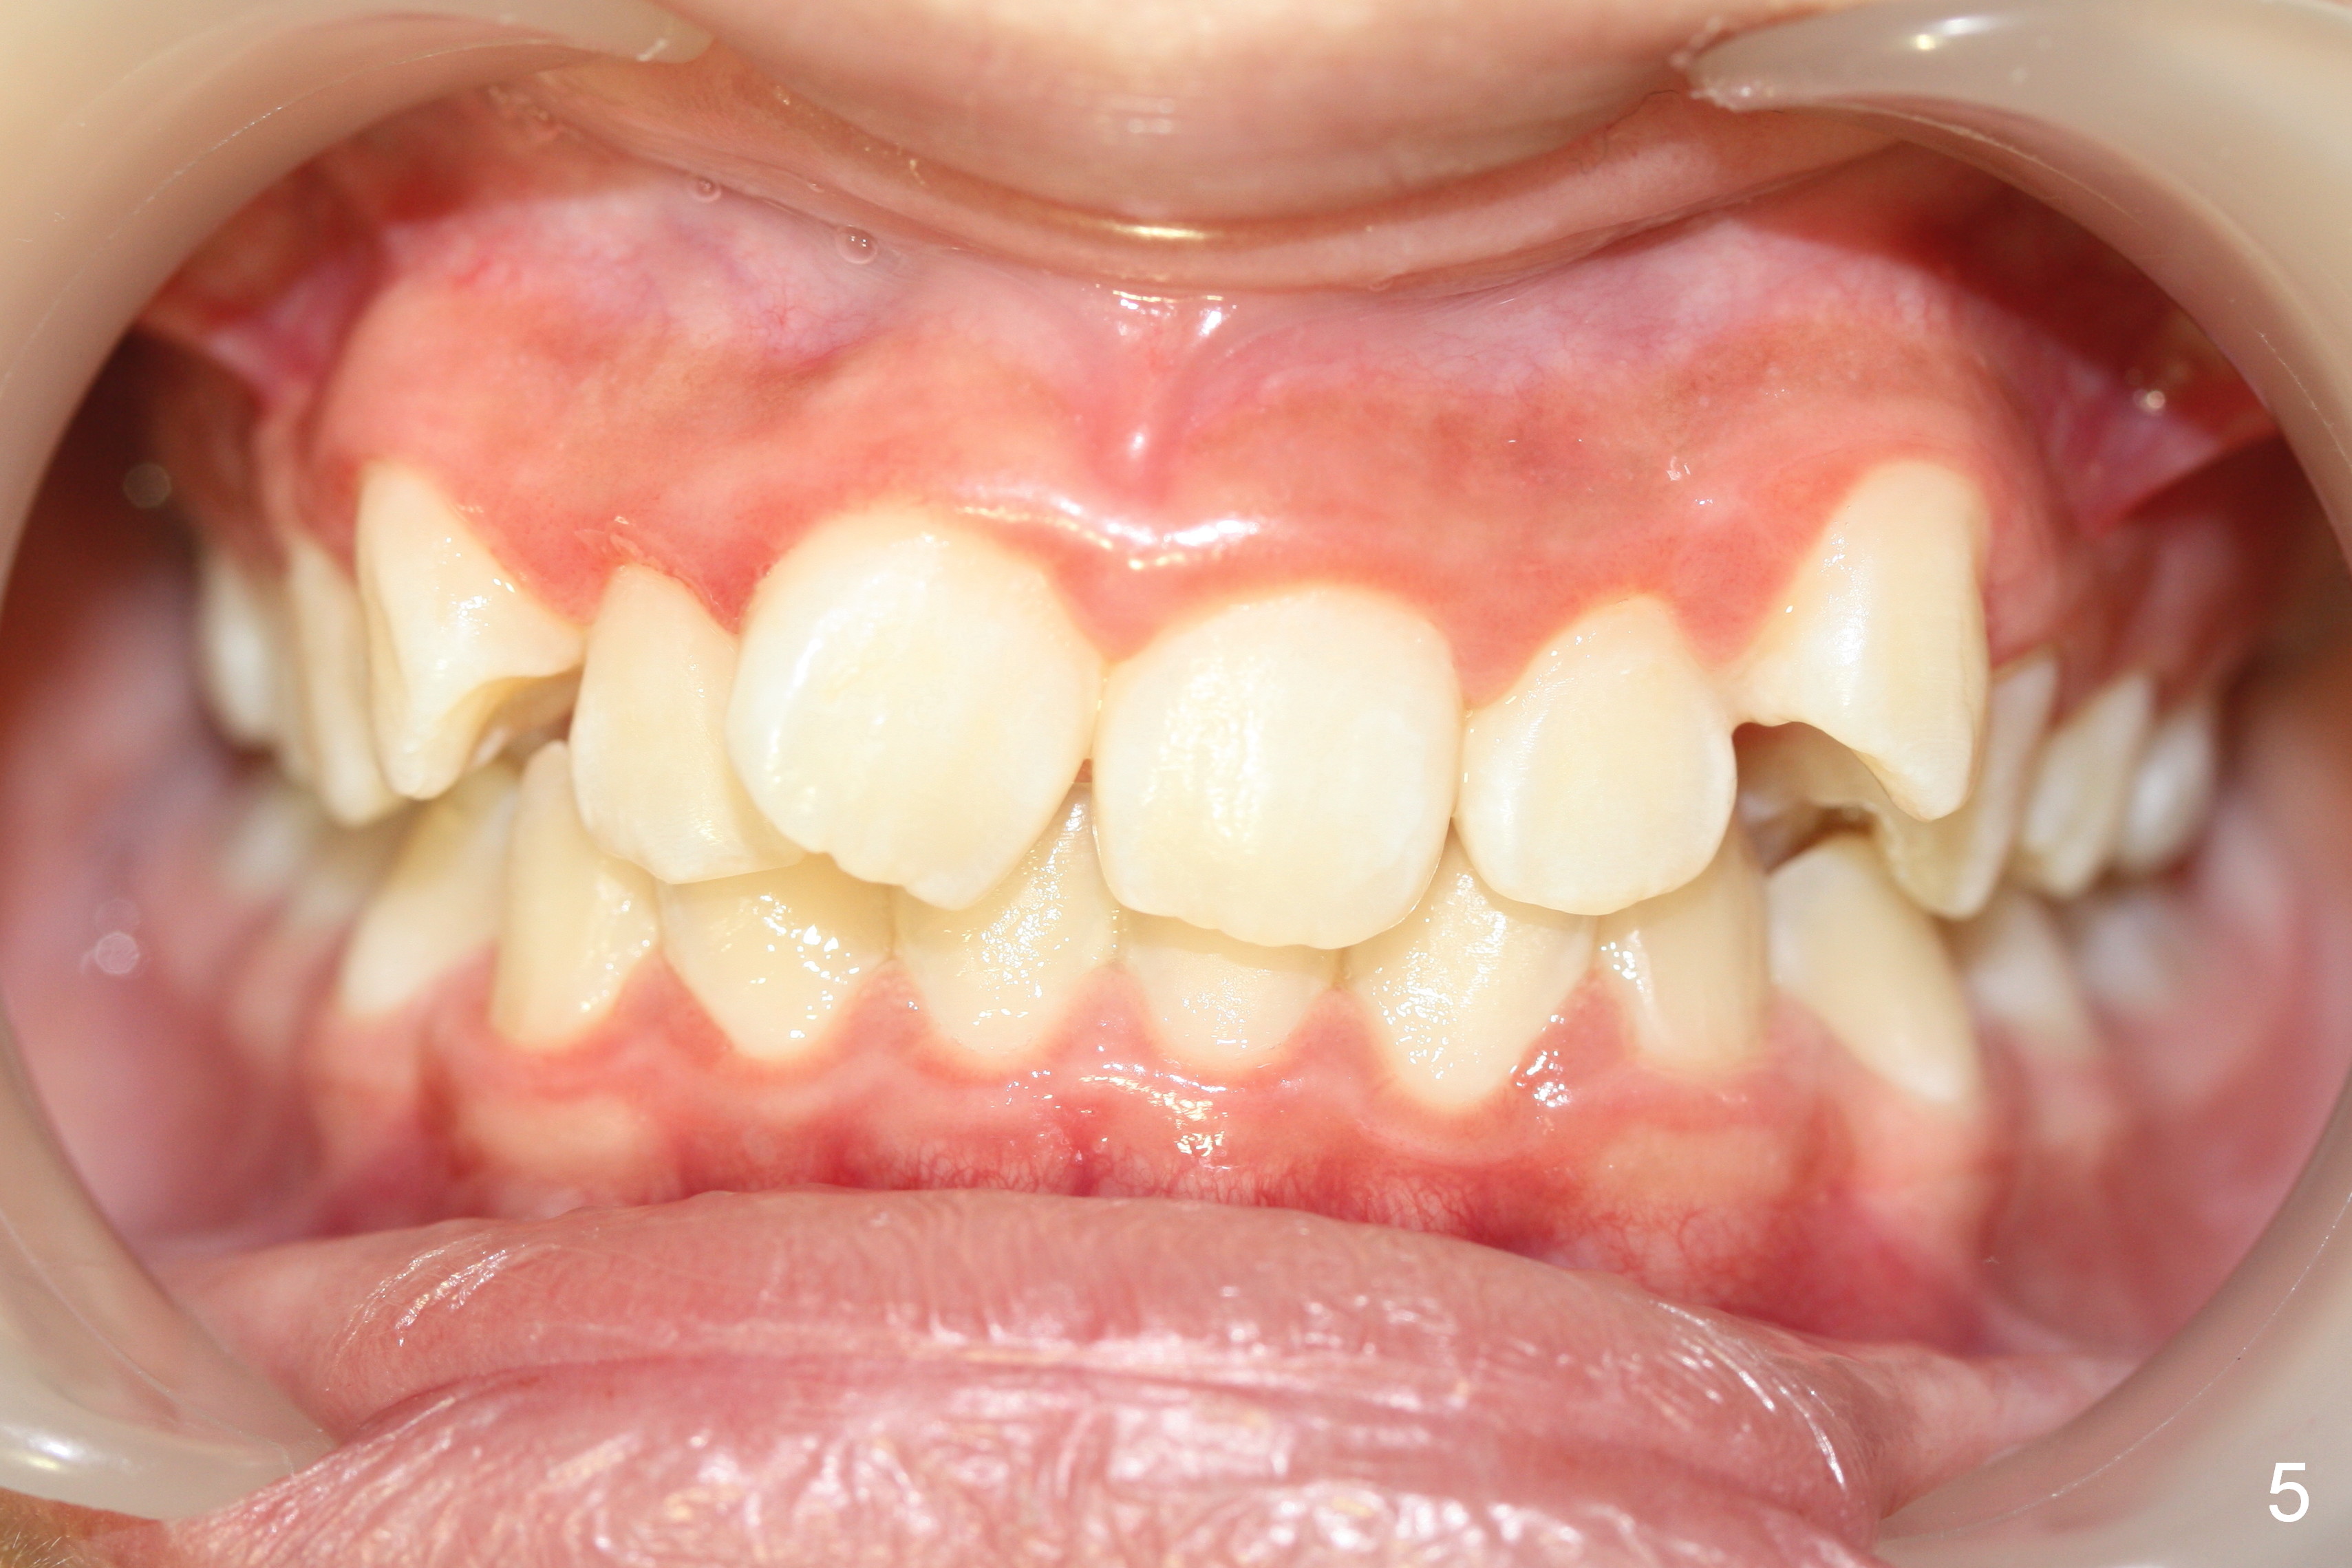

A 13-year-old girl presents for orthodontic consultation.  Chief complaint is crooked teeth.  Her brother is finishing 4 extraction ortho.

Looking at the records, the lower incisors are protrusive and have crowding, so think extraction.  There is enough combined crowding and class II to warrant extraction.  Since there is lower crowding, it would be 4 bicuspid extractions with the sliding mechanics using elastics or Niti closing coil springs. Closing the extraction space by maintaining the lower incisor position and moving the lower molars forward.  The upper arch is 50/50 front going back/back coming forward. Dr. Doug Ness, March 13, 2015 1:18 AM